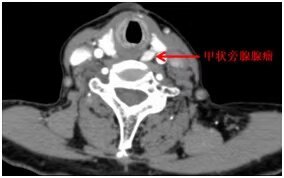

4個(gè)月前,市民李阿姨突然出現(xiàn)咽喉疼痛,聲音也變得嘶啞,多次就診均按慢性咽炎治療,癥狀一直未見好轉(zhuǎn)。 一個(gè)月前,李阿姨來到我院普外科就診,行甲狀腺彩超提示:甲狀腺左側(cè)葉上后方結(jié)節(jié),甲狀旁腺顯像陽性,考慮甲狀旁腺腺瘤或增生。并以“甲狀旁腺腺瘤”收治入院,因阿姨聲音嘶啞持續(xù)加重,普外科請了耳鼻咽喉頭頸外科會(huì)診,經(jīng)電子喉鏡發(fā)現(xiàn)右側(cè)聲帶腫物。兩個(gè)科室醫(yī)師討論過后,經(jīng)患者家屬同意,決定把李阿姨轉(zhuǎn)入耳鼻咽喉頭頸外科進(jìn)行治療。 耳鼻咽喉頭頸外科為李阿姨取了聲帶腫物活檢并送病理,并行頸部增強(qiáng)CT、核磁共振及血鈣、PTH等相關(guān)檢查,確診甲狀旁腺瘤并甲狀旁腺功能亢進(jìn)癥,病理檢查及相關(guān)檢查結(jié)果提示聲帶腫物為良性可能性偏大,這個(gè)結(jié)果讓李阿姨暫時(shí)松了一口氣。 經(jīng)過科室討論,李阿姨出現(xiàn)的兩種問題均為影響其健康需要及時(shí)處理的疾患,在征得李阿姨及其家屬同意下,科室決定為李阿姨實(shí)施手術(shù)同期解除兩種疾患。手術(shù)由耳鼻咽喉頭頸外科李軍政主任團(tuán)隊(duì)實(shí)施,首先,在支撐喉鏡下完整切除了右側(cè)聲帶腫物,并送冰凍,結(jié)果提示為慢性肉芽腫。接著,行頸小切口,在左側(cè)甲狀腺背面找到一枚直徑約1.5cm邊界清楚、表面光滑的腫物,送冰凍,冰凍結(jié)果考慮甲狀旁腺腺瘤。整個(gè)手術(shù)1個(gè)小時(shí)內(nèi)完成,術(shù)后患者生命體征平穩(wěn),安返病房。 術(shù)后病理提示:甲狀旁腺腺瘤;聲帶肉芽腫。第三天李阿姨復(fù)查血鈣濃度已經(jīng)降至正常范圍,術(shù)前不適癥狀基本消失。 “真沒想到脖子里同時(shí)長了兩個(gè)東西,幸虧醫(yī)生及時(shí)發(fā)現(xiàn),還一次就都給切掉了?!毙g(shù)后李阿姨非常激動(dòng)的表達(dá)了對耳鼻咽喉頭頸外科團(tuán)隊(duì)的感謝,也感慨道:以后一定要定期檢查身體,決不能掉以輕心。 甲狀旁腺雖然與甲狀腺僅一字之差,但是它們是兩個(gè)完全不同的內(nèi)分泌器官。甲狀旁腺是人體重要的內(nèi)分泌腺體之一,其分泌的甲狀旁腺激素(PTH)是人體內(nèi)最主要的調(diào)控鈣、磷代謝的激素。甲狀旁腺腺瘤是一種原發(fā)于甲狀旁腺的良性神經(jīng)內(nèi)分泌腫瘤,最常見的表現(xiàn)為原發(fā)性甲狀旁腺功能亢進(jìn)(PHPT),其表現(xiàn)多樣,可表現(xiàn)為泌尿系結(jié)石,骨痛,乏力,腹痛,高鈣血癥、低磷血癥以及骨骼病變等癥狀。所幸李阿姨較早發(fā)現(xiàn)了身體的異常,主動(dòng)前來醫(yī)院檢查,避免引發(fā)更嚴(yán)重的問題。甲狀旁腺腺瘤雖然是良性腫瘤,但甲狀旁腺功能亢進(jìn)會(huì)對人體泌尿及骨骼系統(tǒng)造成嚴(yán)重?fù)p害,因此,一旦確診應(yīng)盡早行到醫(yī)院就診,目前手術(shù)治療是治療甲狀旁腺腺瘤并甲狀旁腺功能亢進(jìn)癥的最有效治療手段。